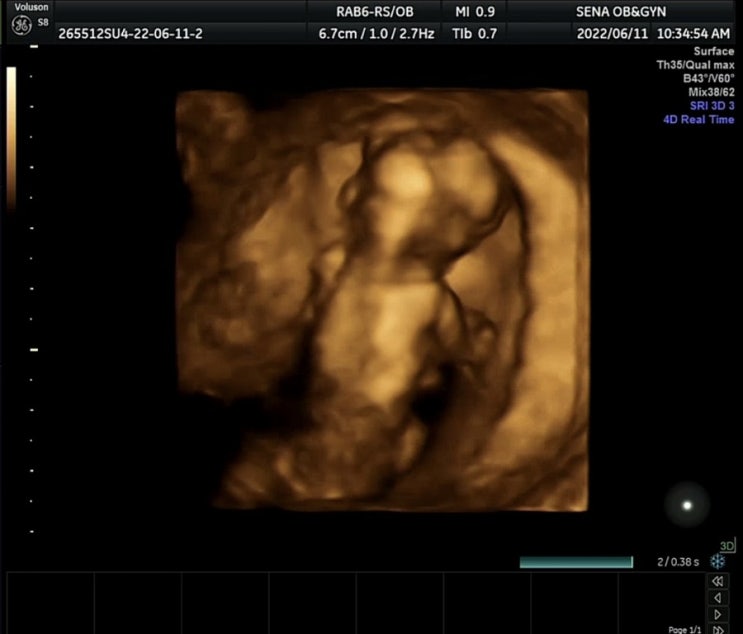

[16주] 2차기형아검사 / 호떡이의 성별은?! / 엄마닮아 엎드린 자세 좋아하는 너

#16주검사 #성별 #2차기형아검사 #각도법 #초음파성별 #성별고수님 오랜만에 남겨보는 임신 일기 그간 일신...